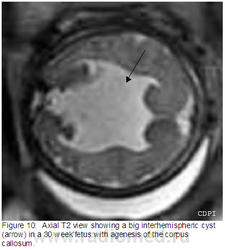

10. На акс.Т2 большая межполушарная киста